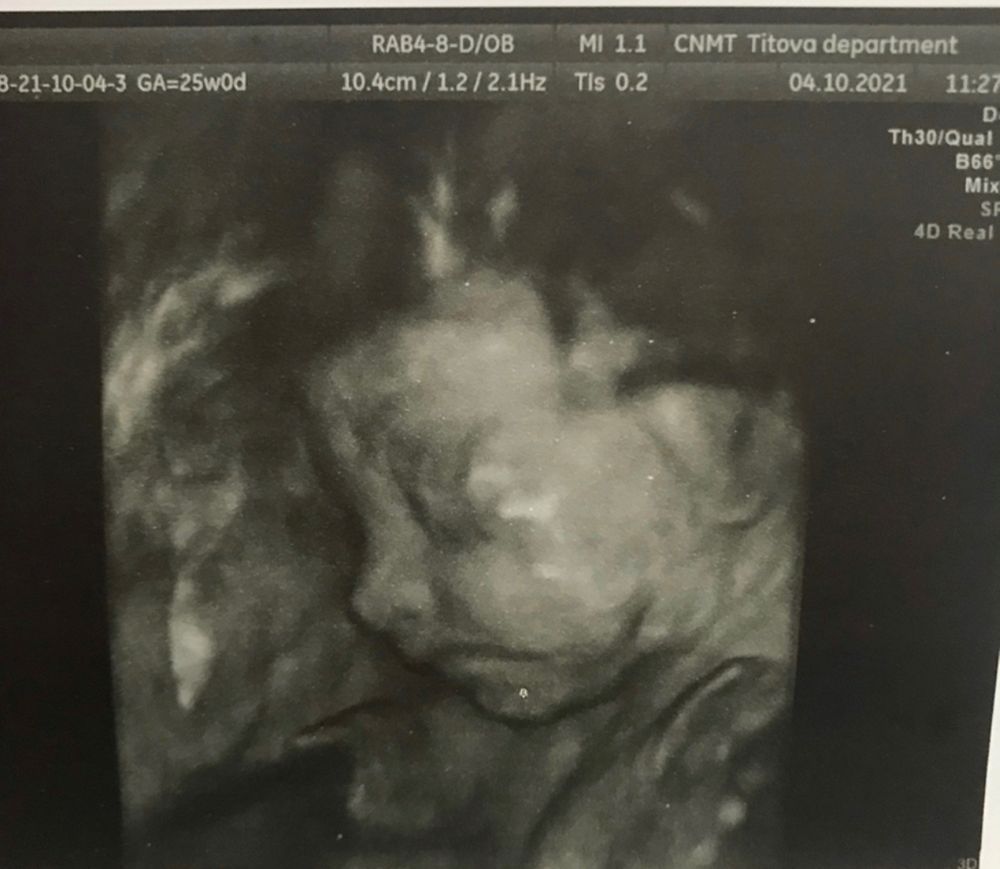

Фотки важных моментов))